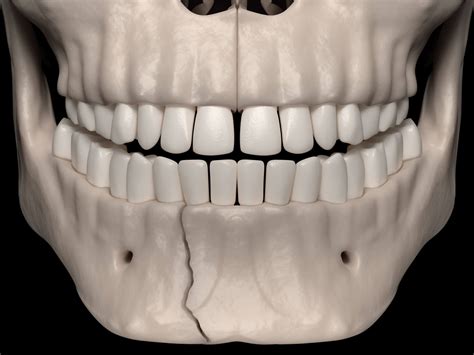

• Mandibular fractures: Breaks in the lower jawbone that impact biting and speech.

• Functional stability: Ensuring the jaw aligns correctly to facilitate proper dental occlusion.